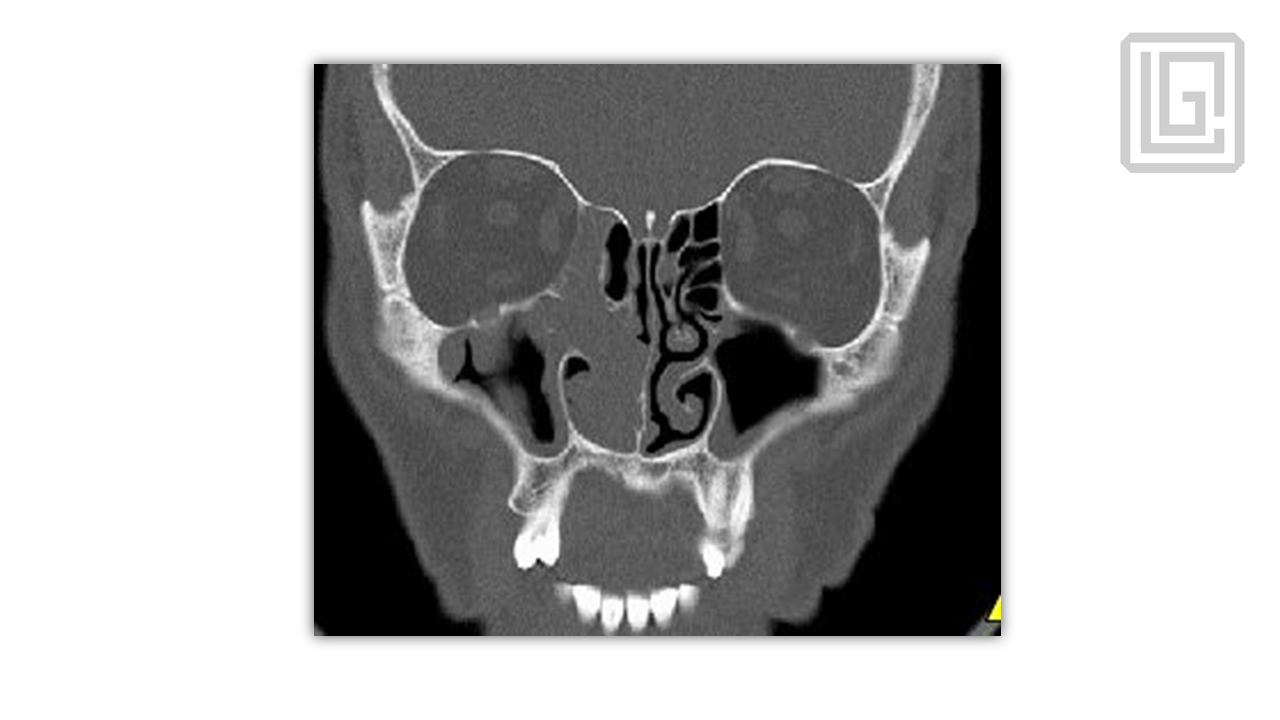

In-depth presentation on the pathophysiology of chronic rhinosinusitis, radiologic planning, sinonasal anatomy, and step-by-step FESS surgical protocol. Covers infundibulum, osteomeatal complex, surgical landmarks, instrumentation, complications, and postoperative management. Presented by Dr. Levon Galstyan.